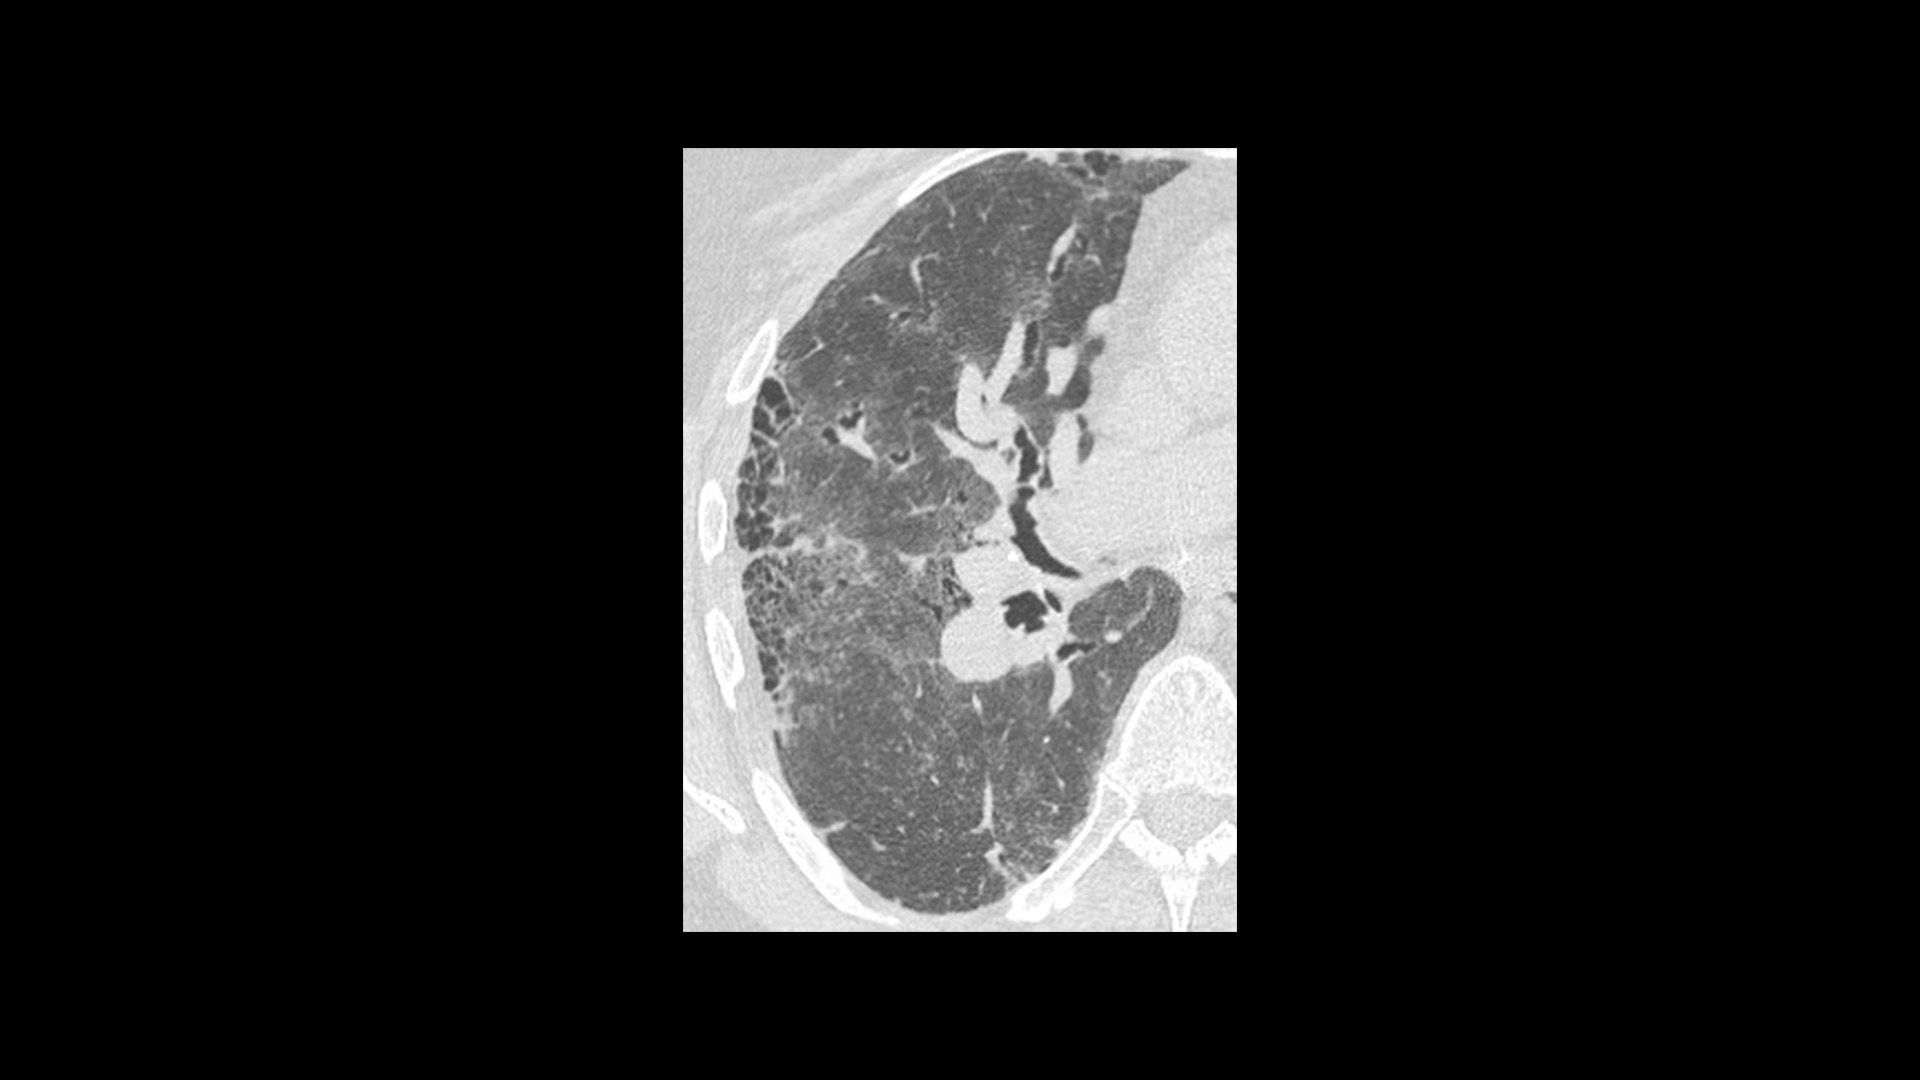

True Enhance DL is a deep learning-based processing method intended for contrast enhancement of single energy images. True Enhance DL uses a dedicated Deep Neural Network (DNN) trained to estimate monochromatic, 50 keV GSI images from single-energy X-ray. This technology brings four deep learning models that the user can choose depending on different contrast enhancement phases by clinical tasks.

TrueFidelity™ DL is our state-of-the-art image reconstruction technology that uses a DNN to generate high-definition, low-noise CT images. It produces images with exceptional sharpness, low-contrast image quality performance and your preferred noise texture, at the same dose.¹